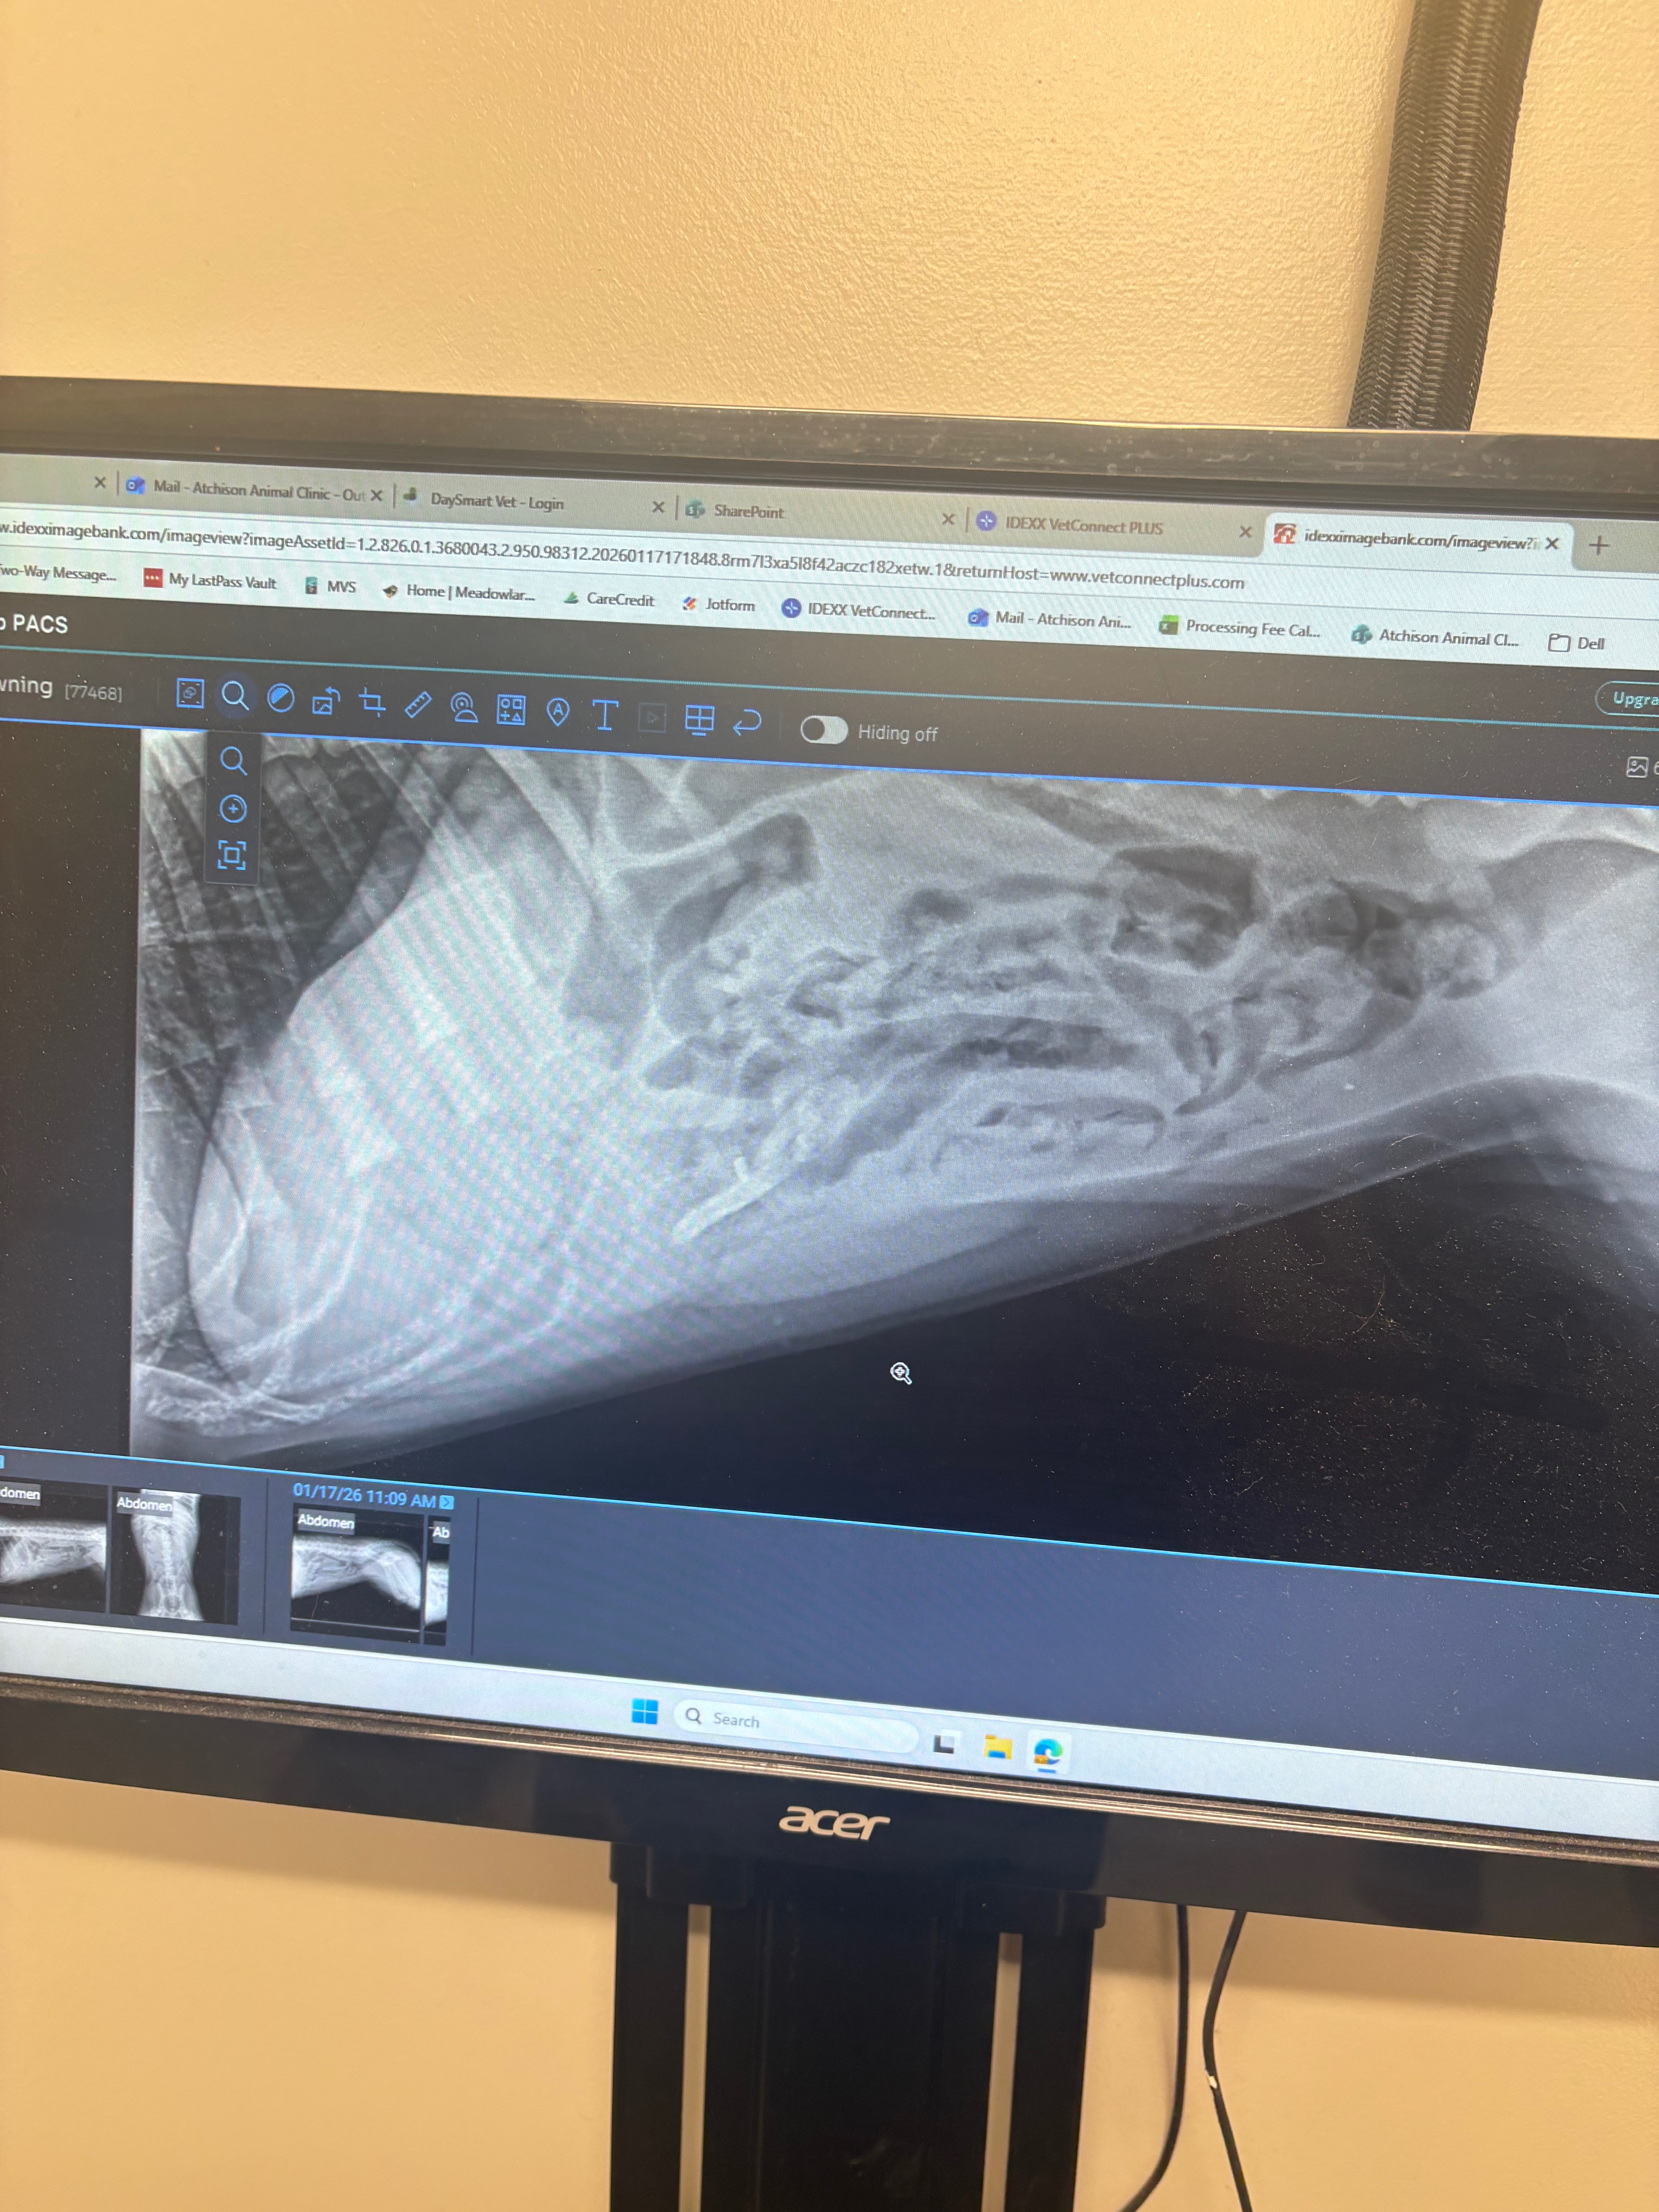

Three days ago, my 5-month-old puppy Peanut suddenly stopped eating. I knew something was wrong, so today we rushed her to the vet. After a series of x-rays and an overnight stay with IV fluids, we received heartbreaking news: Peanut has a severe blockage in her intestines. We’ve already paid for her initial care, but the only way to save her is an urgent surgery that costs much more than we can afford on our own.